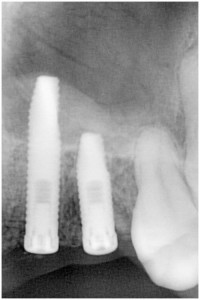

事故により左上34脱落→インプラント埋入

同拡大像

埋入後拡大像